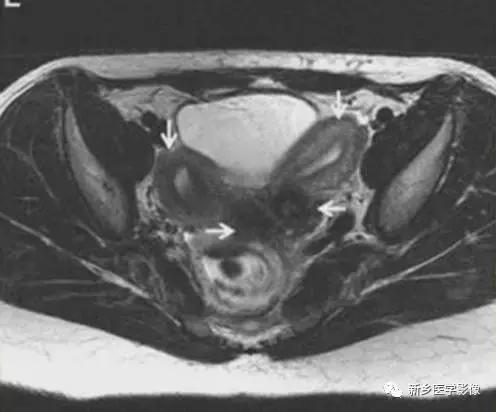

V:纵隔子宫

左图:完全纵隔子宫,纵隔延伸至宫颈内口。

中图:部分纵隔子宫,纵隔未达宫颈内口。

纵隔子宫:宫底轮廓凸出、平坦、轻度凹陷<1cm,肌壁或纵隔深入内膜腔>1cm。

弓形子宫:宫底轮廓凸出、平坦、轻度凹陷<1cm,肌壁或纵隔深入内膜腔<1cm。

完全型纵隔子宫:短T2信号纵隔贯穿宫腔,宫颈管及阴道上段。

MR诊断为完全型纵隔子宫伴阴道纵隔。

完全型纵隔子宫:宫底平坦,纵隔贯穿宫腔和宫颈

不完全型纵隔子宫:宫底平坦,纵隔未达宫颈内口水平